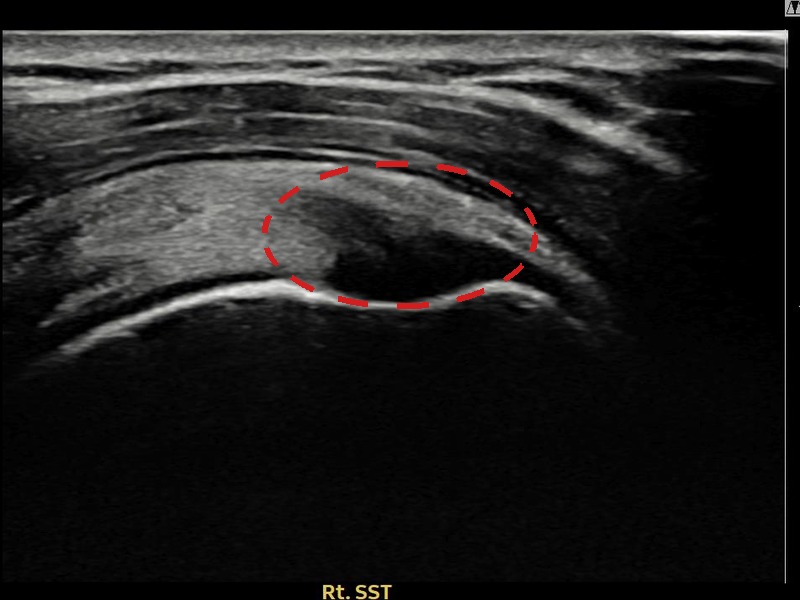

김ㅇㅇ님 · 우측 극상근건 관절면측 부분파열

우측 어깨 통증이 일상 동작에서 지속되어 내원하셨습니다. 초음파 검사에서 극상근건 관절면측 부분파열 확인 후 축소봉합술을 시행하였고 구조적 회복이 이루어졌습니다.